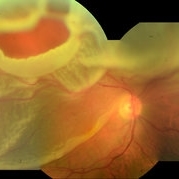

Rhegmatogenous Retinal Detachment Rhegmatogenous Retinal DetachmentOct 8 2019 by DIEGO TOLENTINO Rhegmatogenous retinal detachment, macula off. Photographer: Diego Tolentino